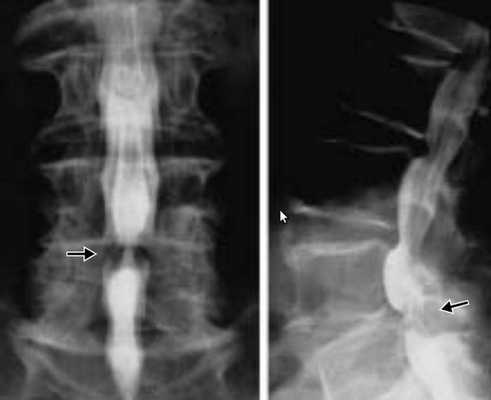

- рентгенография пояснично-крестцового отдела позвоночника;

Позвоночный стеноз диагностируют по совокупности выявленных признаков сужения позвоночного канала при наличии характерных клинических данных.

Исследование проводится с использованием функциональных проб в двух проекциях для обнаружения вертебральных патологий — спондилеза, гипермобильности, подвывихов шейных суставных отростков, аномалий строения. Рентгенография наиболее информативна при остеохондрозе. На полученных изображениях отчетливо визуализируется уменьшение промежутков между позвонками, изменение их формы с образованием остеофитов.